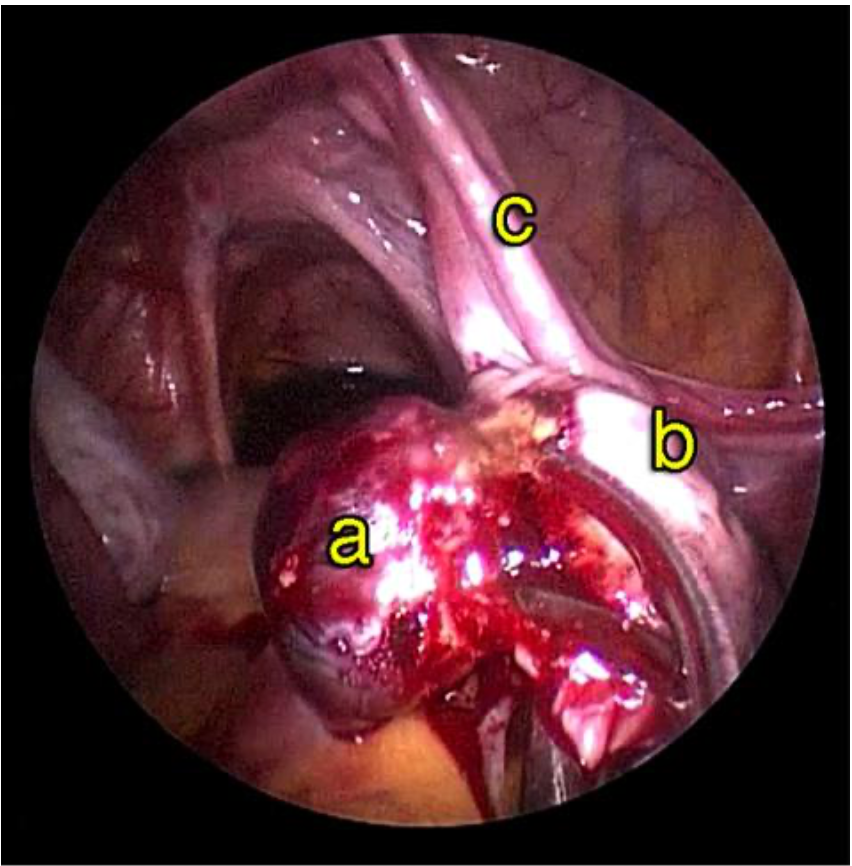

Saat kehamilan ektopik berada di daerah kornu rahim ( Gambar 7.4 ), maka kehamilan biasanya didiagnosis masih lama lagi. Kehamilan kornu jauh lebih sulit untuk dieksisi secara laparoskopi karena ukuranya lebih besar dan dapat berdarah dengan menyebar luas. Teknik ini melibatakan suntikan vasopressin disekitar kornu kehamilan ektopik dan penempatan jahitan purse string di sekitarnya. Kemudian sayatan dibuat untuk enukleasi kehamilan ektopik. kerusakan kemudian dijahit. Pada kehamilan kornu yang besar, bagian dari rahim harus diangkat bersama-sama dengan tuba. Pada kasus- kasus yang sulit, laparotomi mungkin diperlukan.

Reseksi laparoskopi kornu kehamilan ektopik

Pada tahun 2009 nyonya UDS datang mengunjungi saya , dia telah menikah 3 tahun dan dia tidak bisa hamil. Histerosalpingogram yang dilakukan di rumah sakit yang lain menunjukkan kedua tubanya tersumbat / terblokir. Dia menjalani laparoskopi , dan laparoskopi menunjukkan ukuran rahim yang normal. Kedua tuba nya normal dan dipatenkan setelah insulfasi tuba dilakukan dibawah tekanan. Dia hamil secara spontan 2 bulan setelah menjalani laparoskopi namun sayangnya kehamilan berakhir dengan aborsi yang terlewatkan. Dia telah menjalani evakuasi hasil konseptus. Pasca operasi , keadaan dia baik-baik saja akan tetapi tidak dapat hamil. Dia telah diberikan beberapa siklus klomifen sitrat namun tanpa membuahkan hasil. Pada tahun 2011, dia menjalani siklus inseminasi intrauterin setelah diberikan suntikan hormon perangsang folikel ( FSH ). Setelah prosedur dilakukan , dia hamil akan tetapi sayangnya kehamilan itu adalah kehamilan ektopik. Dia menjalani reseksi laparoskopi kornu kanan kehamilan ektopik di tahun 2011 ( Gambar 26.7 – 26.11 ) ( simak video 26.3 ). Pasca operasi di tahun 2013 dia menjalani histerosalpingografi dan menunjukkan bahwa tuba kiri tidak paten. Dia dapat hamil setelah menjalani IVF.

Kornu kehamilan ektopik tidaklah umum. Biasanya didiagnosisnya terlambat karena pasien dengan kondisi seperti ini tidak memliki banyak gejala-gejala. Pecahnya kehamilan ektopik pada kornu dapat menyebabkan pendarahan yang berlebihan. Pada pasien ini diagnosis dilakukan lebih awal karena dia menjalani IUI dan berada dalam pengawasan secara teratur. Eksisi telah dilakukan dengan berhasil secara laparoskopi.